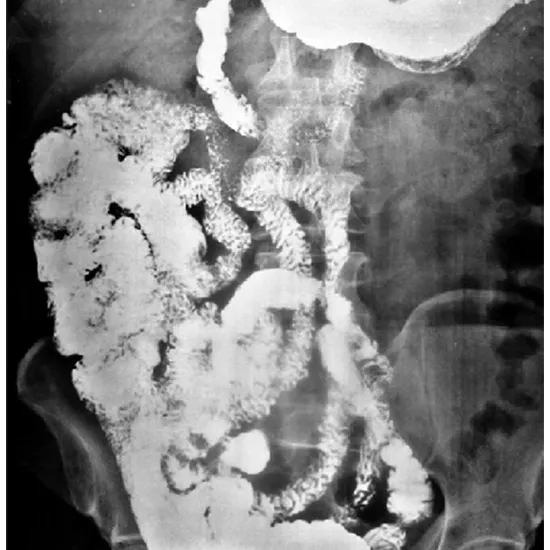

Barium bowel follow through test is diagnostic imaging technique used to detect the presence of tumours of the small bowel, bowel obstructions or inflammatory disease of the small intestine (Crohn's disease)

A barium swallow follow through test is an X-Ray examination of the small bowel which connects the stomach to the large intestine.